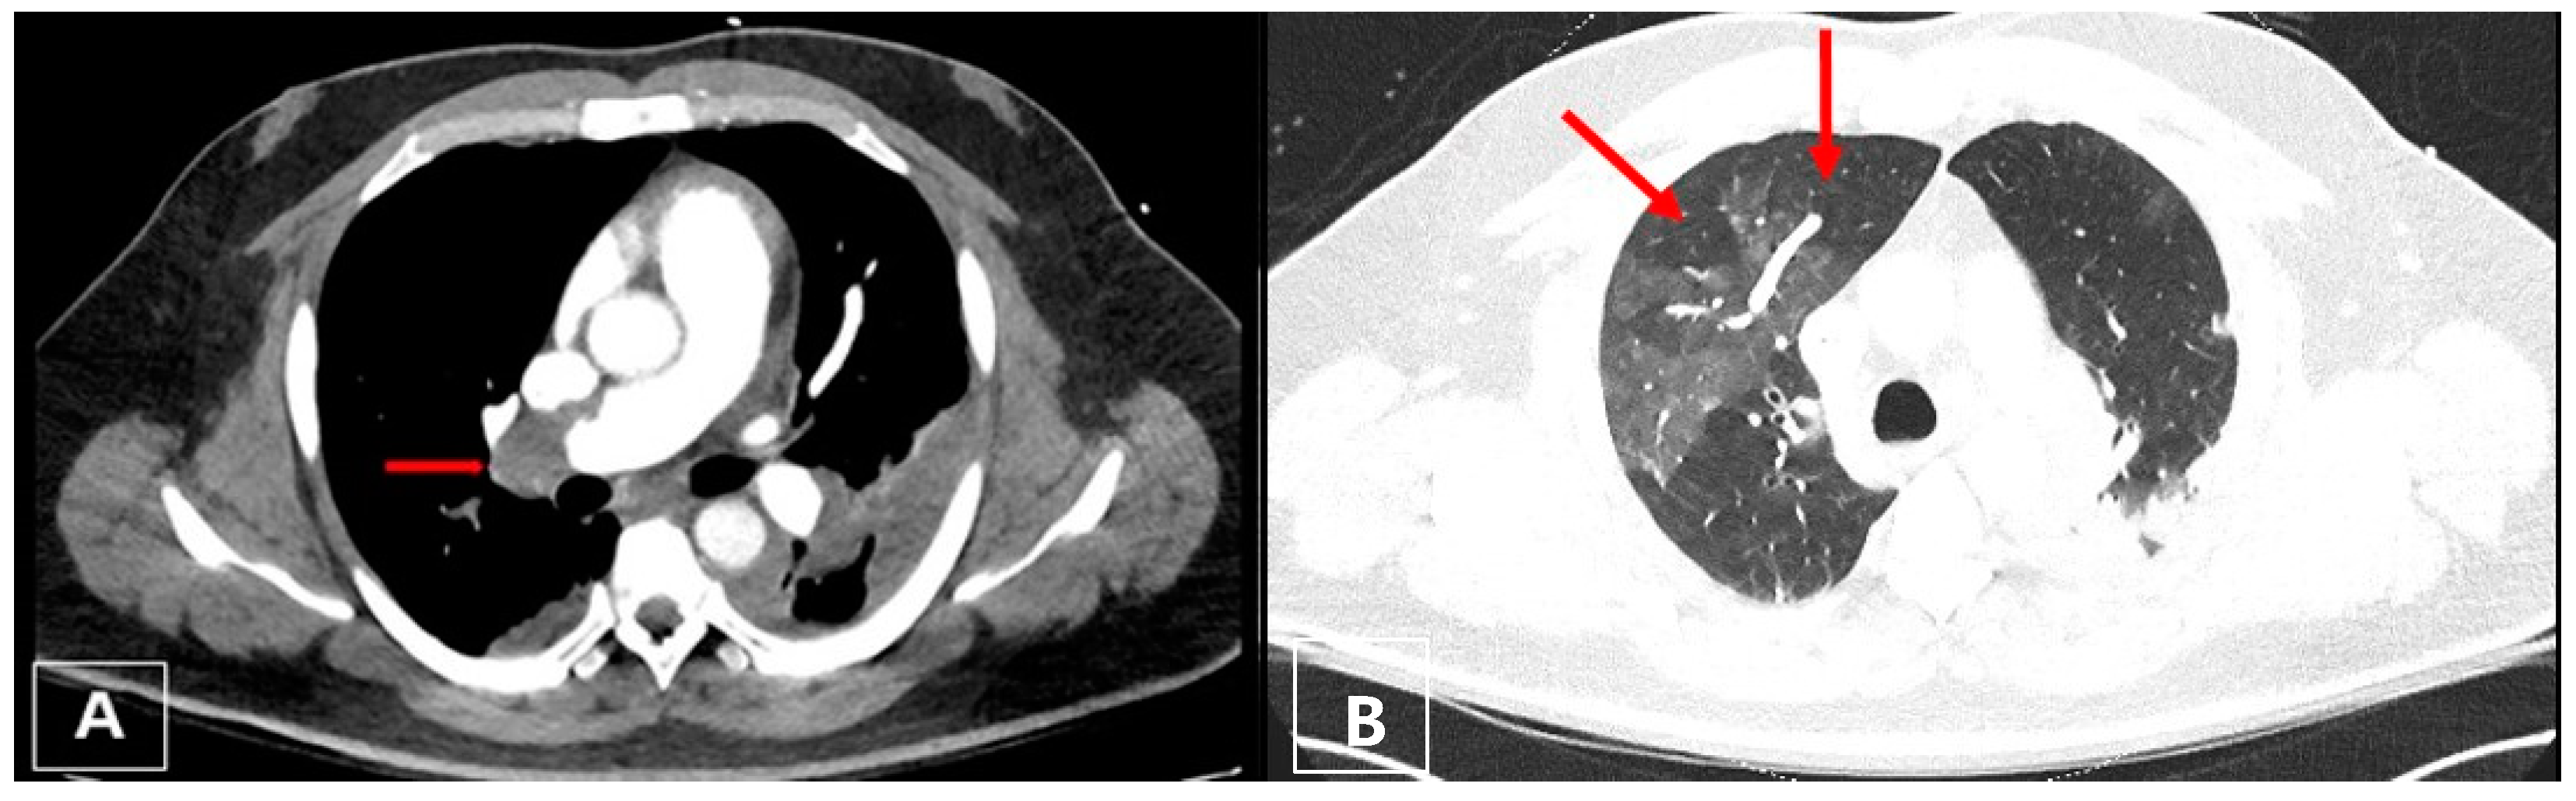

2.1. Case 1

2.2. Case 2

3.4. Computed Tomography Pulmonary Angiography (CTPA)